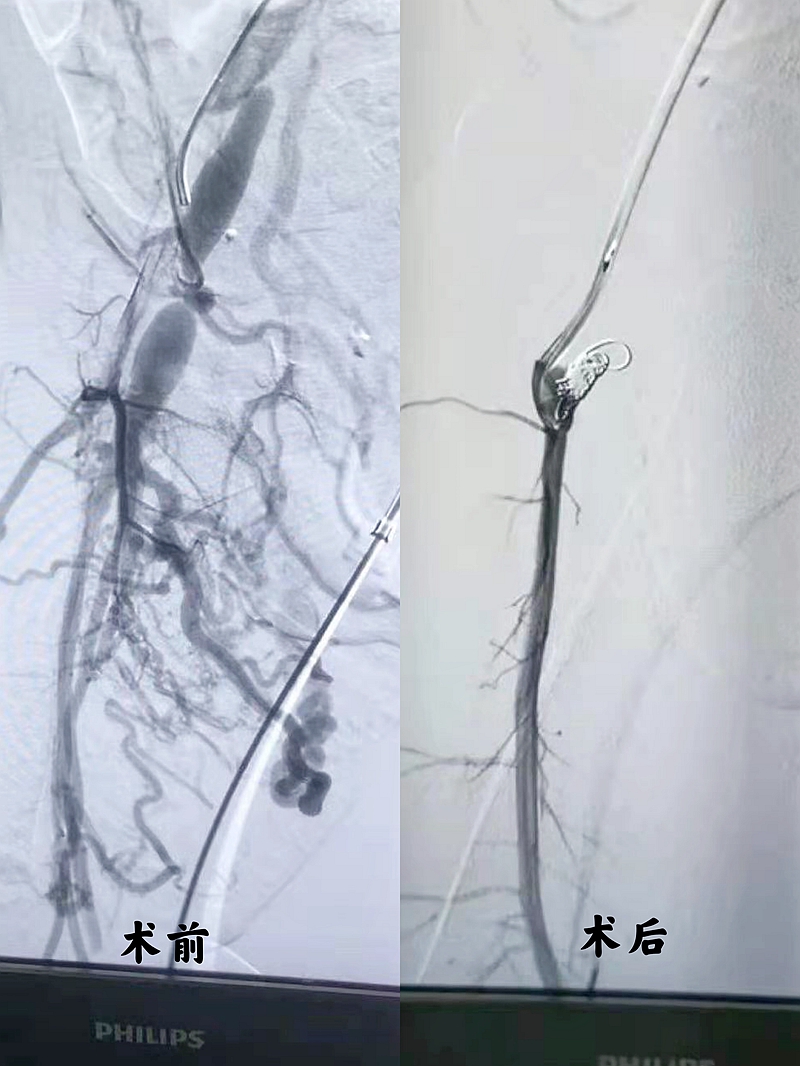

术前术后血管形态对比图

经缜密的术前准备工作,龙岗妇幼第一例血管介入手术顺利实施了。小杰所接受的右侧股动静脉瘘介入封堵术,具有安全有效、创伤小、并发症少、复发率低、住院时间短等优点,这对于幼小的生命来说无疑是最好的选择。整个术程3小时,术后造影复查股动静脉瘘口消失,小杰生命体征平稳。